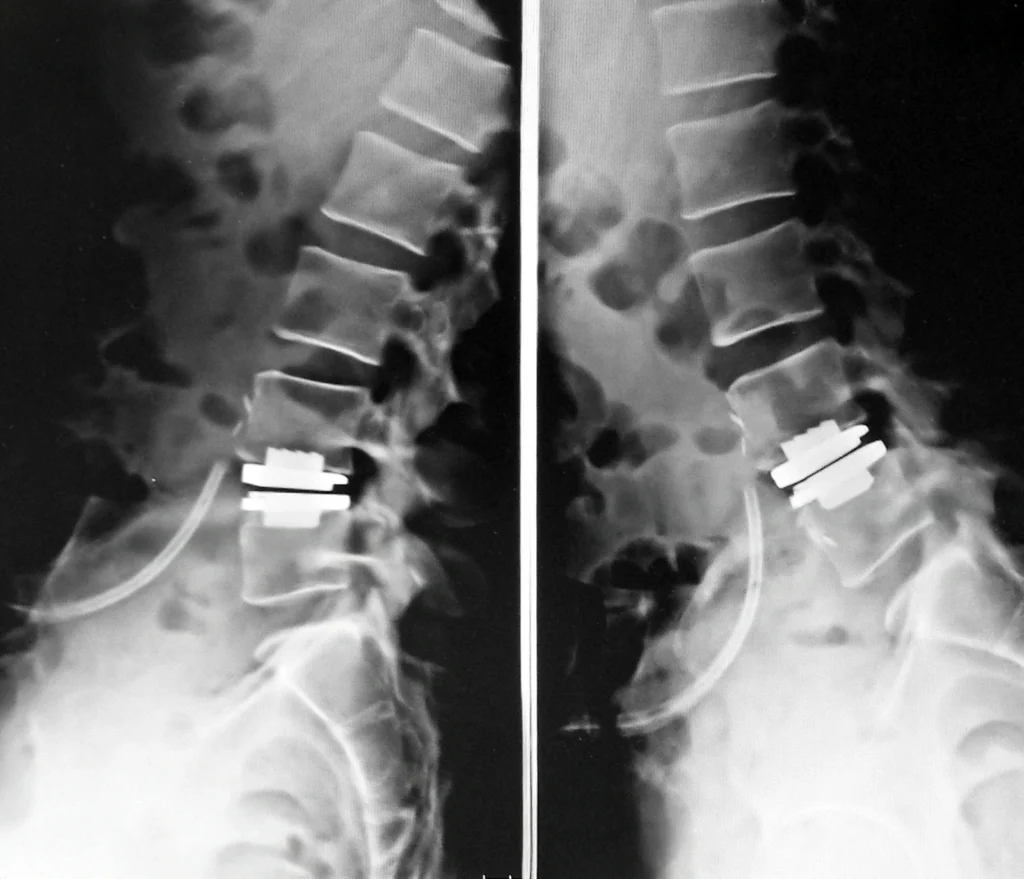

Sostituzione totale di disco lombare (protesi di disco)

In una selezione di pazienti affetti da lombalgia meccanica discogena, cioè un dolore lombare cronico legato principalmente alla sofferenza di uno o più dischi intervertebrali, la Neurochirurgia di Villa dei Fiori può proporre la sostituzione totale di disco lombare (Total Disc Replacement).

Questa procedura è indicata soprattutto in pazienti relativamente giovani o in età lavorativa, con dolore lombare resistente alla fisioterapia e alle terapie conservative, e con un disco singolarmente compromesso. L’intervento prevede un accesso anteriore mini-invasivo all’addome, attraverso il quale si rimuove il disco malato e lo si sostituisce con una protesi artificiale. A differenza dell’artrodesi tradizionale, la protesi di disco mantiene la mobilità del segmento trattato, preserva l’altezza dello spazio discale e la fisiologica curvatura lombare, riducendo il sovraccarico sui dischi adiacenti.

Il decorso è generalmente rapido: il paziente viene mobilizzato precocemente, non necessita di busti o tutori e può tornare alle proprie attività in tempi brevi, con un significativo miglioramento del dolore lombare.